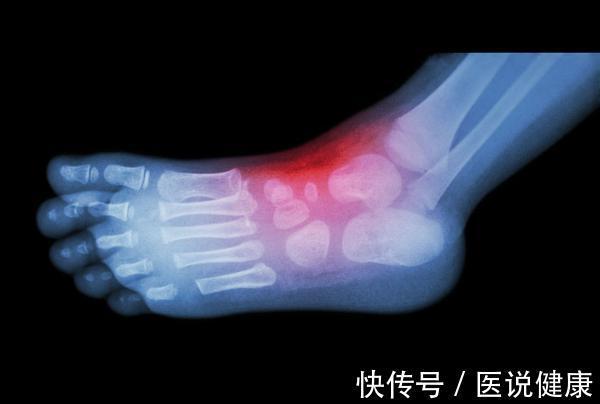

这种关节炎疾病就是建立在了高尿酸血症的基础上,由于患者体内的血尿酸水平超标,大量尿酸析出了单钠尿酸盐结晶,它们在患者的关节不断堆积,最终促使关节出现急性炎症反应,痛风因此发作。

就目前临床掌握的资料来看,高尿酸血症一旦析出了尿酸盐结晶、在关节处沉积,急性痛风发作仅仅只是时间问题而已。